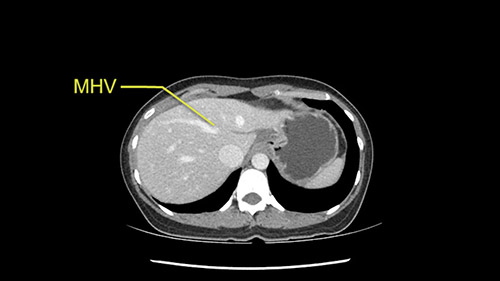

Anatomically, to plan for a left lateral segmentectomy, it’s relatively easy as far as liver surgery goes. I know that I'm going to be looking for the left hepatic vein which will be divided at some point either towards the end at the back near the vena cava or through the middle of the left lateral segment.

Preserve middle hepatic vein

The transection line will be a little more obvious. There’s a little patch of focal fat here in Segment 4b but we’ll describe the transection line probably through the mid portion of Segments 4a and b up to the top. Up at the top, the left hepatic vein can be taken. There’s a Segment 3 vein or the so-called falciform vein it’ll be rudimentary so I think we’ll be able to get around the left hepatic vein and leave the middle [hepatic] vein intact because it’s free of tumor.

Her vein, it looks like a combined middle and left hepatic vein, it may be encircled during the case as a whole common trunk but most probably it will not be a big deal because if it is okay to go with the left lateral resection, the vein or the left hepatic vein can be catched during the intraparenchymal dissection and can be controlled in that side.

So in terms of planning on the surgery, I think there’s two clear options for this patient and that we’ll need to assess once we’re in the operating room. One option would be to do a Segment 3 resection. This tumor seems like it's hanging from Segment 3 so I think if we can get a good margin, that would be an option. Of course the other option is to do a left hepatectomy, preserving the middle hepatic vein, which is clearly not involved with the tumor.

The other option of course is to do an anatomical left hepatectomy. In that case, I will start mobilizing of course the left lobe and try to find the ligamentum venosum, take it down and go around the left hepatic vein. I think, importantly in these cases and in this case, as you can see in the venous phase, that’s clearly a moment to stop. Because the left hepatic vein is pretty close to the middle hepatic vein as sometimes it is so you may need to dissect a little bit the parenchyma on top of the left hepatic vein to be able to go around the left hepatic vein safely.